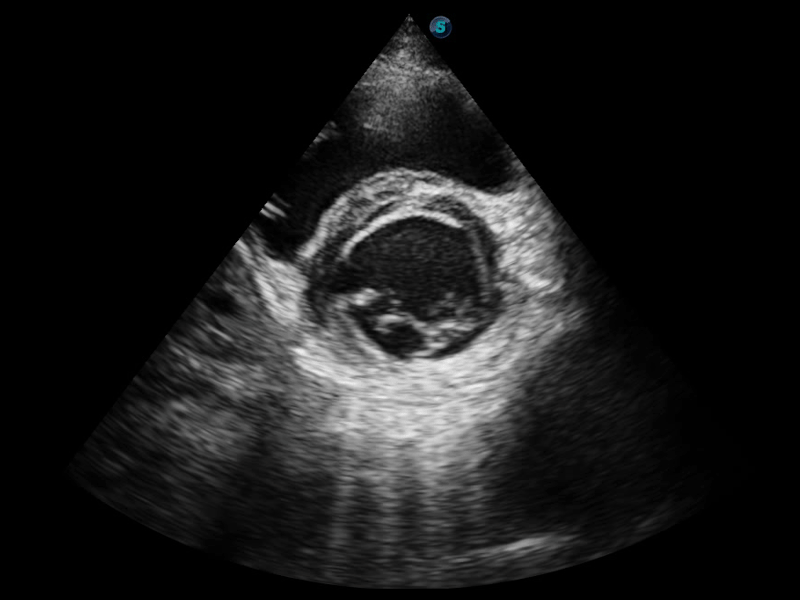

開立醫(yī)療通過不斷的技術(shù)創(chuàng)新,為大眾的生命健康提供持續(xù)關(guān)愛。P12 Plus采用全新一代超聲成像平臺(tái),新平臺(tái)旨在將真實(shí)還原組織解剖結(jié)構(gòu)作為首要目標(biāo)。平臺(tái)采用全新集成化硬件模塊,搭載新一代芯片,系統(tǒng)性能得到大幅提升,為您的診斷提供了豐富的臨床信息。優(yōu)異的圖像表現(xiàn),豐富的探頭配置,全面的應(yīng)用功能,為您日常診斷提供了可靠的助手。

P12 Plus

彩色多普勒超聲診斷系統(tǒng)